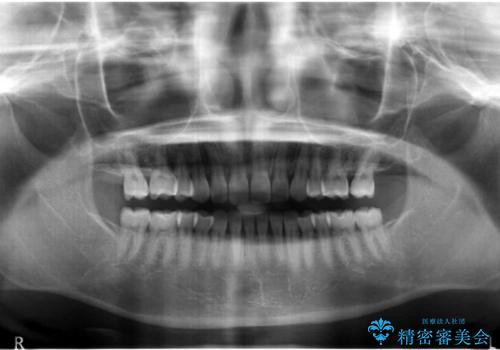

前歯のすきま 右上の小臼歯の垂直的骨吸収を抜歯で解決

レントゲンで、右上4番の近心の垂直的骨欠損があり、抜歯を行うこととしました。

垂直的骨欠損は咬み合わせから起こったものと推察されました。

short faceであり、結果上顎の臼歯を近心に大きくロスさせることになったたため、非常に長く治療期間はかかりました。

右上4の垂直性骨欠損については再生療法を行う選択肢もありました。

しかし、過蓋咬合であり、咬頭対咬頭の咬合では根本的な解決は見込めないことから、矯正治療を希望されていたこともあり、相談の上抜歯しました。